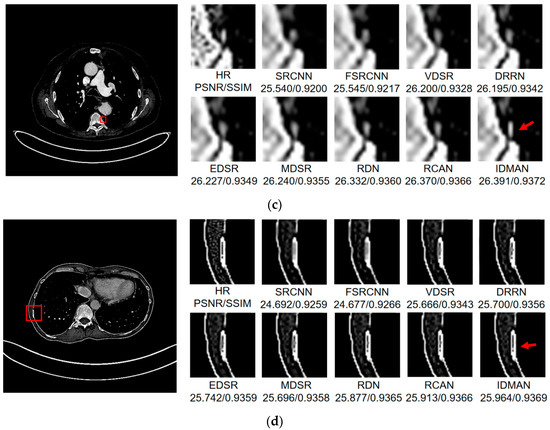

Visual Results: In order to analyze the reconstructed CT image from the subjective visual effect, we select several groups of CT image for a contrast display in Figure 8, Figure 9 and Figure 10.

Figure 8.

Images (a–d) show the visual results of different algorithms on DeepLesion testing set for scaling factor .

Figure 9.

Images (a,b) show the visual results of different algorithms on DeepLesion testing set for scaling factor .

On the whole, The IDMAN proposed in this paper can reconstruct clearer edges and more realistic textures. Under the scale SR, as shown in Figure 8a, it is clear that the image reconstructed by IDMAN has a more realistic texture and a better visual effect. In Figure 8b, the reconstructed SR image can restore more truthful details than other methods. In Figure 8c, the image reconstructed by the contrast method is blurred, while the reconstructed result by our method has sharpener edges and more detail. In Figure 8d, the reconstructed image has a clearer and smoother edge. Under 3 scale SR, from Figure 9a, it can be seen that the structure of the reconstructed image by other algorithms is more unclear, while the reconstructed result of IDMAN is more realistic. In Figure 9b, our reconstructed image has a more restored effect with clearer and more accurate contour lines, compared to other methods. Under the scale SR, we can observe, from Figure 10a, that the result of our method can better restore the original information and is more similar to the original image. In Figure 10b, it is clear that IDMAN can reconstruct a clearer edge but the images of other methods appear more blurred. Our proposed model achieved better results in the CT image dataset. The reconstructed CT image of our method has more details, and PSNR and SSIM also achieved higher scores.

It can be clearly observed that the reconstruction effect of SRCNN with only three layers is the worst among these methods based on deep learning, with problems such as blurring, artifacts, a lack of detail, unclear edges and so on. The later improved models are becoming more and more complex by deepening the network or using different learning strategies, and the reconstructed results have a clearer structure which is better than SRCNN. Additionally, our IDMAN has a superior learning ability, and the reconstructed results become to have more details and sharper edges. The better visual reconstruction results also prove that we can use information distillation and multi-scale attention to help the network make full use of the feature information more effectively, and capture more information to restore more details.